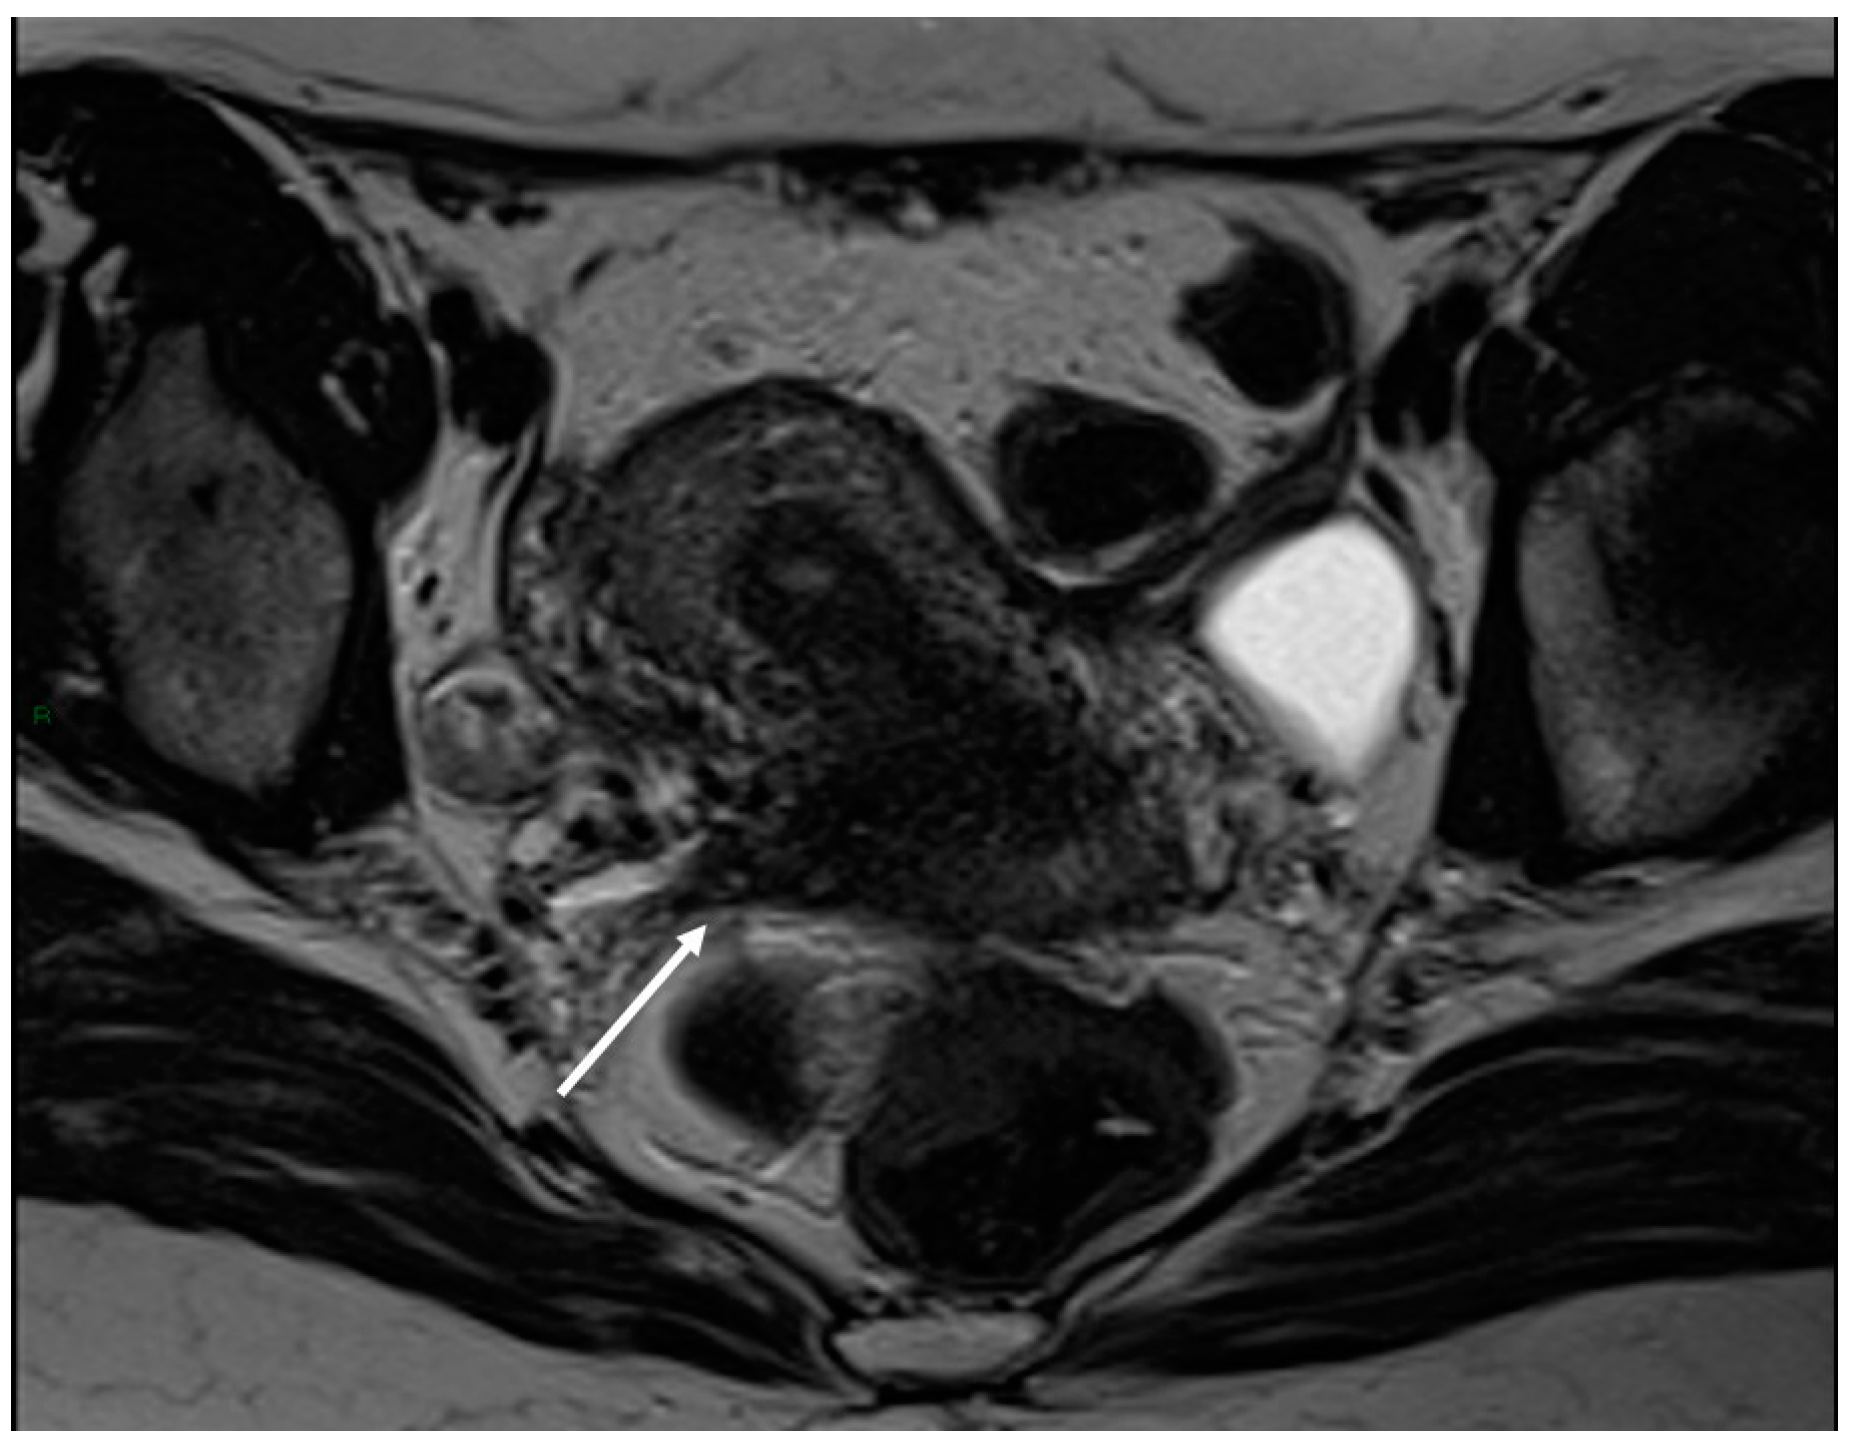

6.4. Neural Involvement

There are also cases of involvement of peripheral nerve plexuses of the pelvic region, such as sciatic, obturator, femoral, and pudendal nerves and their branches (Figure 14).

Figure 14.

Localization of the left sciatic nerve and para-uterine endometriotic nodule in a 43-year-olf female with a previously diagnosed endometriosis and surgery approach, accepted at the emergency department for reported left lumbar pain, which radiates to the left side and is associated with episodes of vomiting. (A) Coronal T2WI. Involvement of peripheral nerve plexuses of the pelvic region (sciatic nerve) appearing as a hypointense plaque (white arrow); (B) Coronal fat-suppressed T1WI. The lesion shows small hematic foci (white arrow); (C) Axial T2WI. Para-uterine endometriotic nodule (white dotted arrow) shows variable intensity ranging from low intensity (referred to as shading) to intermediate or high intensity; (D) Axial T1WI. Para-uterine endometriotic nodule with hyperintense signal (white dotted arrow).

MRI is the best imaging modality to investigate neural involvement [78].